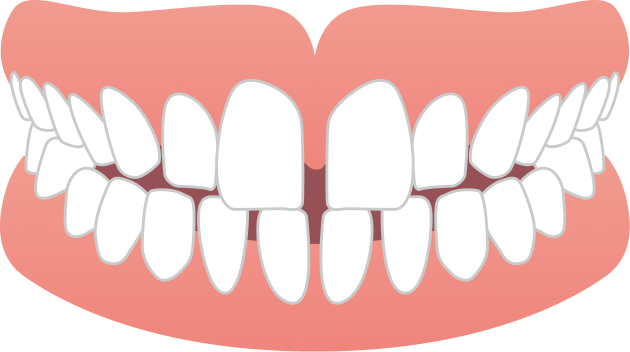

BEFORE

| 年齢・性別 | 20代女性 |

|---|---|

| 主訴 | 前歯のガタガタと噛み合わせが気になる |

| 施術内容 | 歯全体のマウスピース矯正システム「インビザラインフル」を用いた治療 |

| 治療期間 | 1年8ヶ月 |

| 費用 | 924,000円(税込) |

| リスク/副作用 | 全ての方で、疼痛、咬合痛、歯根吸収、歯肉退縮、歯髄壊死が生じる可能性があります。 |

| その他注意点 | 指定した時間、マウスピースをつけていただけない場合は治療期間が長くなる場合があります。 |